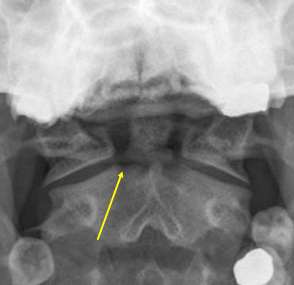

Jefferson Fx

Comminuted atlas fx as a result of axial loading, e.g. landing on one’s head or abruptly on one’s feet

Ant. and post. arches of C1 are fx

Post-op halo

Jefferson fractures are indicated by asymmetry in the odontoid view with displacement of the _____ away from the dens.

Lateral masses